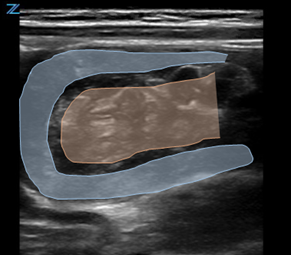

Classically, intussusception manifests in the transverse orientation as a ‘target sign’ or ‘donut sign’ (Figure 1) representing layers of intestine within the intestine. In the longitudinal orientation, the layers of intestine appear as a ‘pitchfork’ or ‘submarine sandwich’ (Figure 2). These findings are most commonly seen in the right lower quadrant for ileocolic intussusception, which is the most common type of intussusception. Small bowel intussusceptions can be differentiated by their size, which are often ≤3 cm.5 While small bowel intussusceptions often spontaneously reduce, if symptoms and findings persist, computed tomography (CT) may be necessary to determine management. POCUS is useful in differentiating variants of intussusception that range from a surgical emergency to a transient source of abdominal pain allowing clinicians to better manage these patients.6

Figure 2. Pitchfork Sign on longitudinal image of intussusception